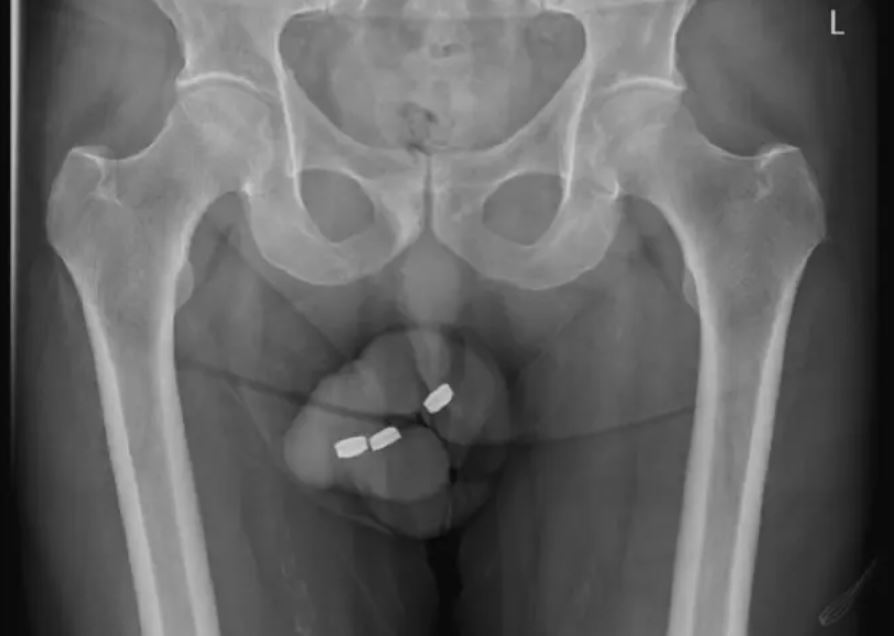

Ένας 73χρονος άνδρας από την Αυστραλία χρειάστηκε να υποβληθεί σε χειρουργική επέμβαση στην ουρήθρα, προκειμένου να αφαιρεθούν από το εσωτερικό τρεις μπαταρίες. Η περίπτωση του άνδρα, έγινε θέμα επιστημονικής μελέτης στο περιοδικό Urology Case Reports, αφού προσπαθούσε να τροφοδοτήσει τη σεξουαλική του ικανοποίηση τοποθετώντας τις μπαταρίες στην ουρήθρα του.

Ύστερα από το περιστατικό με τις μπαταρίες ο 73χρονος ζήτησε βοήθεια έπειτα από 24 ώρες, με τους γιατρούς να κινούνται γρήγορα, ώστε να αφαιρέσουν τα ξένα σώματα, αφού η διαβρωτικότητά τους μπορεί να επιφέρει νέκρωση στους ιστούς μέσα σε μόλις δύο ώρες.

Ύστερα από πολλές ανεπιτυχείς προσπάθειες οι γιατροί κατάφεραν τελικά με λαβίδες να αφαιρέσουν τις μπαταρίες από την ουρήθρα του άνδρα.

«Όλες οι εξαγόμενες μπαταρίες ήταν επικαλυμμένες με ένα μαύρο υλικό που έμοιαζε με πίσσα», σημειώνεται στη μελέτη.